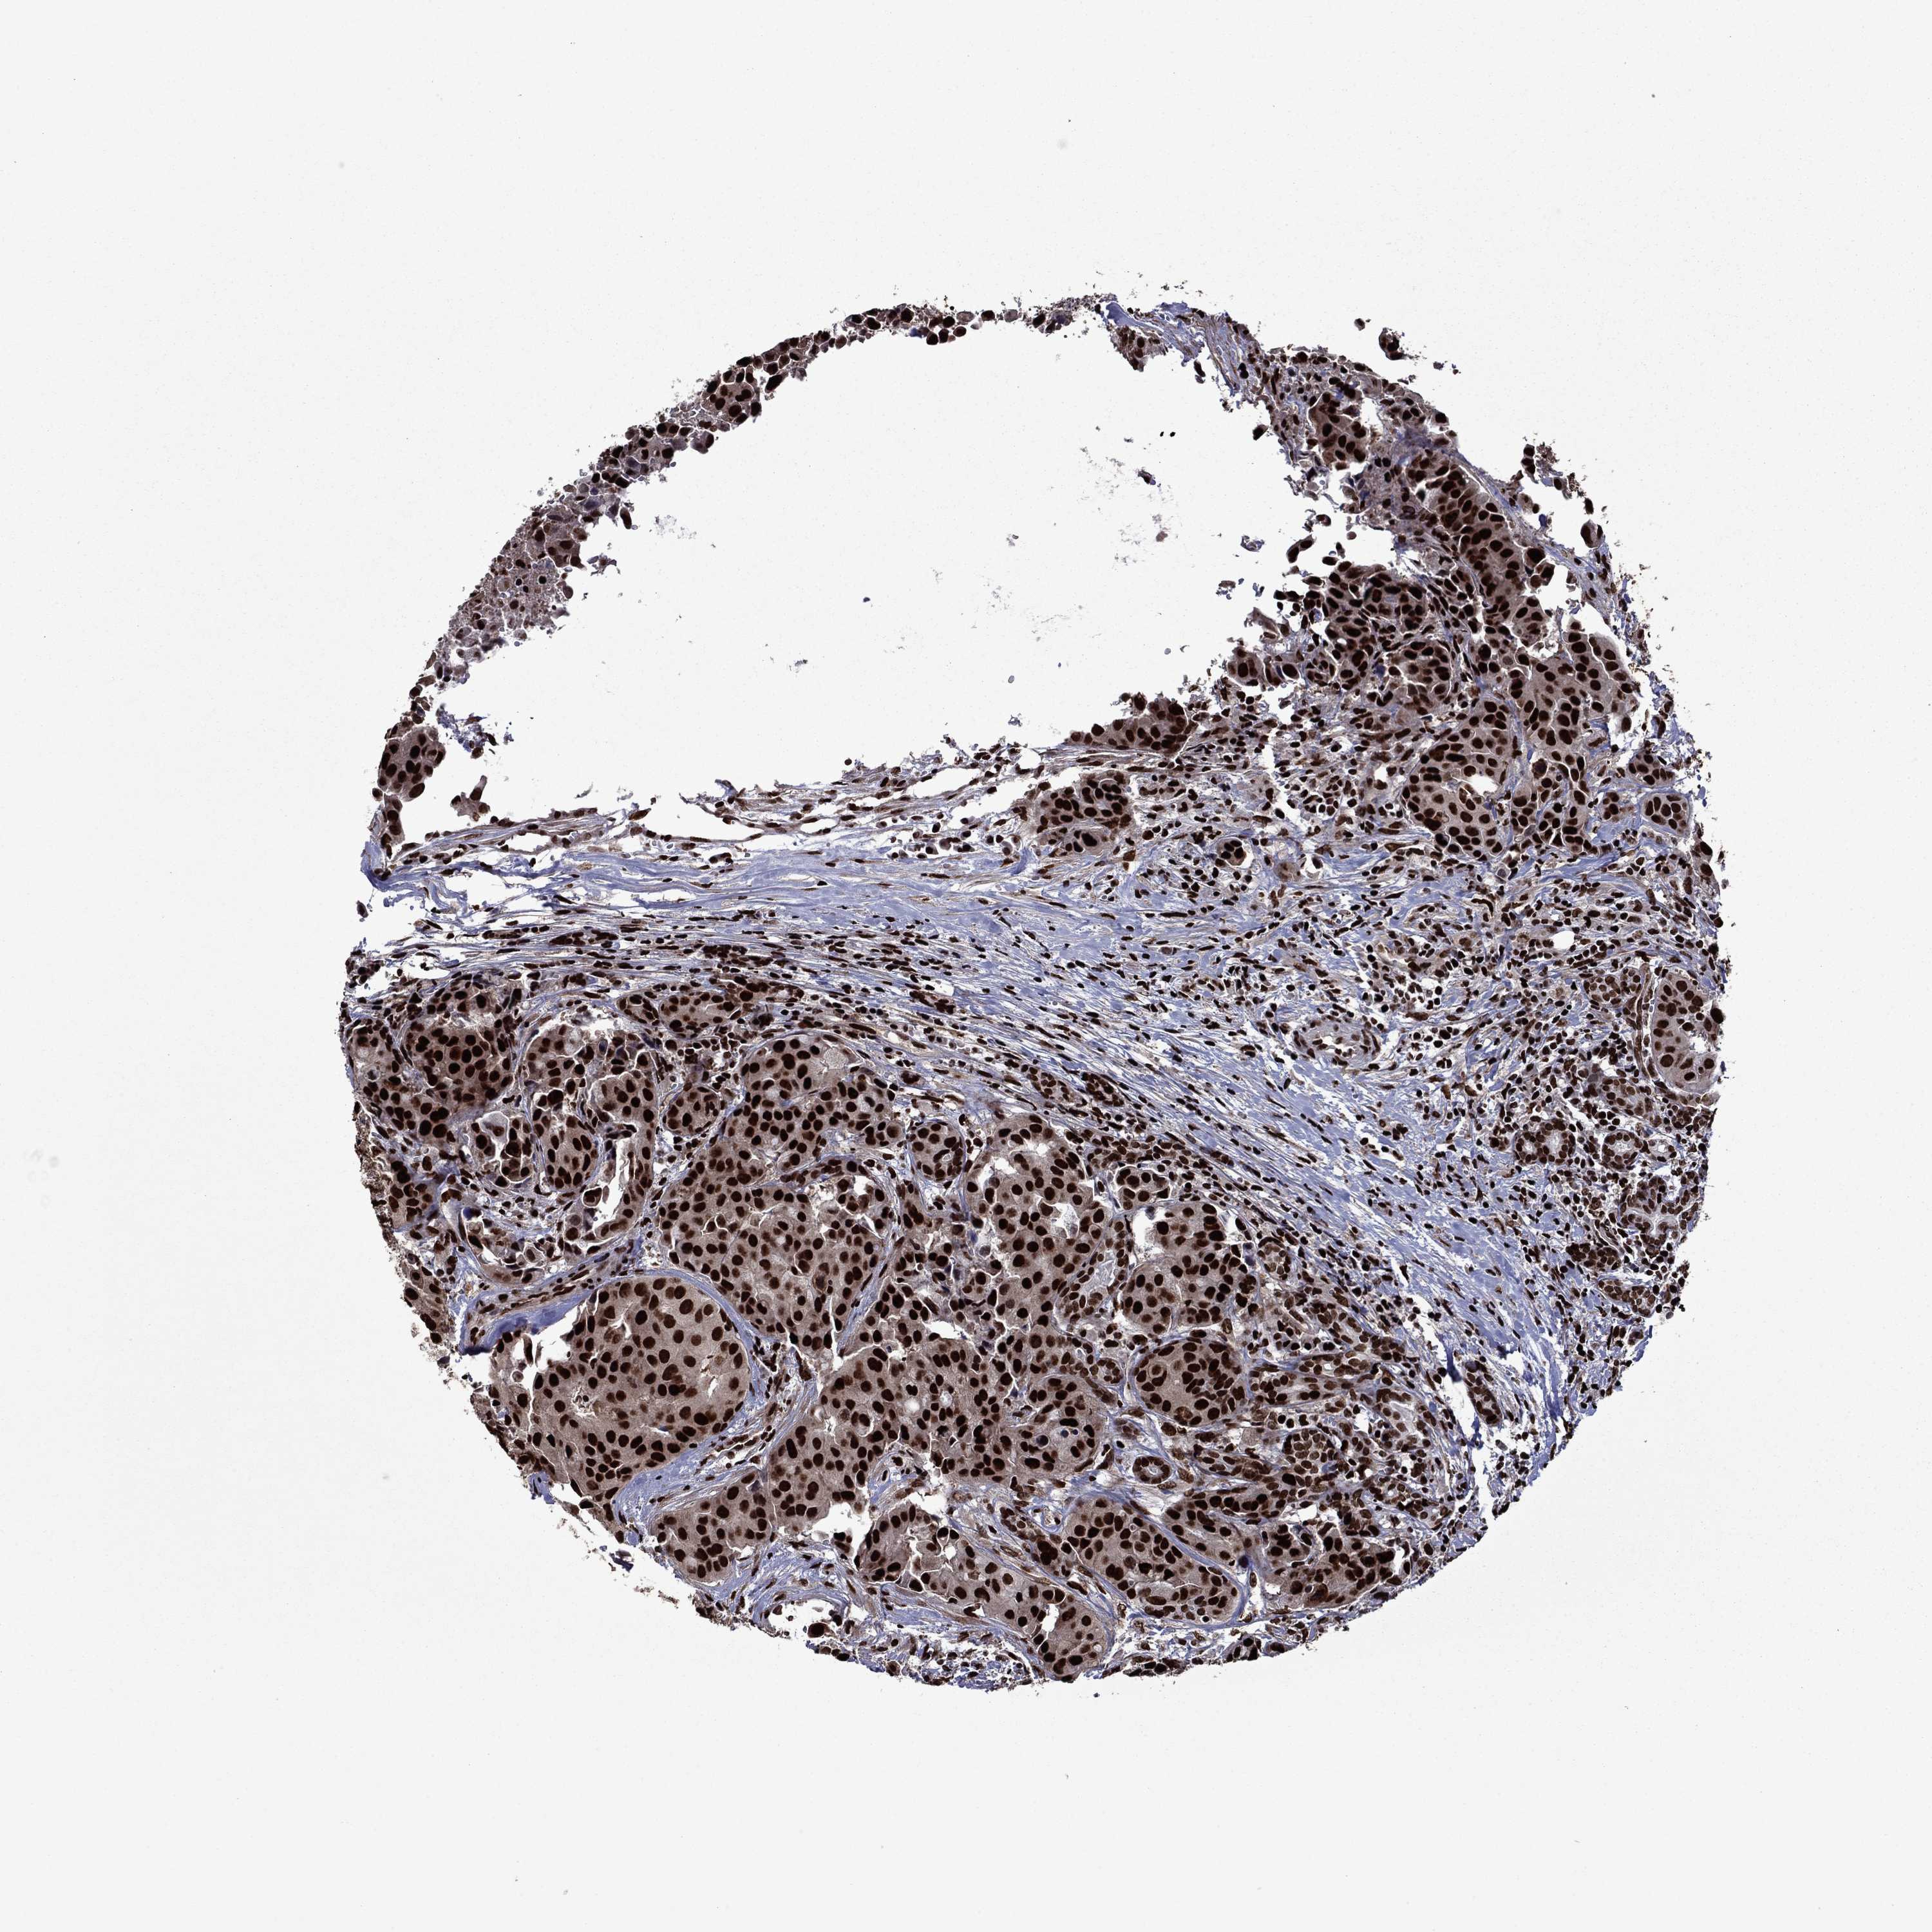

HEAD AND NECK CANCER - Protein expressioni

A mouse-over function shows sample information and annotation data. Click on an image to view it in a full screen mode. Samples can be filtered based on level of antibody staining by selecting one or several of the following categories: high, medium, low and not detected. The assay and annotation is described here.

Antibody stainingi

Antibody staining in the annotated cell types in the current human tissue is reported as not detected, low, medium, or high, based on conventional immunohistochemistry profiling in selected tissues. This score is based on the combination of the staining intensity and fraction of stained cells.

Each image is clickable and will lead to virtual microscopy that enables deeper exploration of all samples and also displays staining intensity scores, fraction scores and subcellular localization as well as patient and tissue information for each sample.

Antibody HPA073571

Staining

High

Medium

Low

Not detected

Intensity

Strong

Moderate

Weak

Negative

Quantity

>75%

75%-25%

<25%

None

Location

Nuclear

Cytoplasmic/membranous

Cytoplasmic/membranous,nuclear

Squamous cell carcinoma, NOS